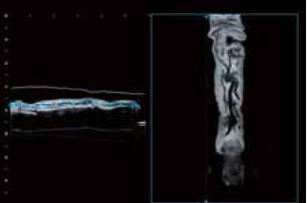

Пальці

На Рис.4 показані зображення нормального пальця. Кровоносні судини, кістки і нігті можна чітко розпізнати за допомогою Smart Sensor 3D (рис. 4а). Shadow Glass також виявився корисним в ортопедичних обстеженнях, наприклад, для візуалізації переломів. Зображення Shadow Glass можуть бути клінічно кориснішими, ніж звичайні зображення, оскільки на одному зображенні можна отримати більше інформації.

Крім того, використання вигнутої С-площини, створеної OmniView (рис. 4б), дозволяє зобразити кровоносні судини в пальцях безперервно. Таким чином, цілісність кровоносних судин можна оцінити, використовуючи як 3D Shadow Glass (рис. 4в, г), так і 2D вигнуту С-площину. Планується, що ці зображення виявляться корисними в широкому спектрі клінічних досліджень, таких як мікрохірургія.

a) Багатоплощинна реконструкція (MPR) та яскравість

б) Вигнута С-площина (OmniView)

в) Shadow Glass: Долоня

г) Shadow Glass: Тильна

Рисунок 4. Нормальні пальці з використанням Smart Sensor 3D